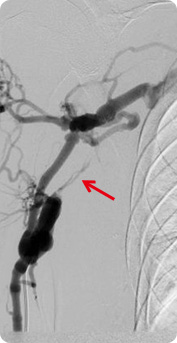

(Dialysis)- ① Hemodialysis

polycystic renal disease, glomerulonephritis, old age, obesity, and hyperlipidemia for over 3 months, it is diagnosed as chronic renal disease (chronic renal failure) If the condition deteriorates and kidney becomes completely dysfunctional, it is called end-stage renal failure, and the most common practice for this occasion is hemodialysis.

Some of the blood is drawn out to dialysis machine to be filtered of waste and then put back into the body. It is conducted about 3 times (4 hours for each session) weekly.